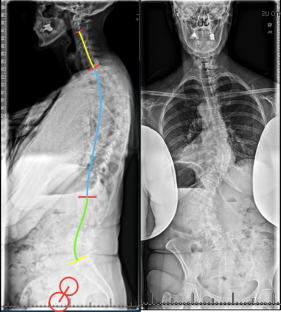

Fig. 2